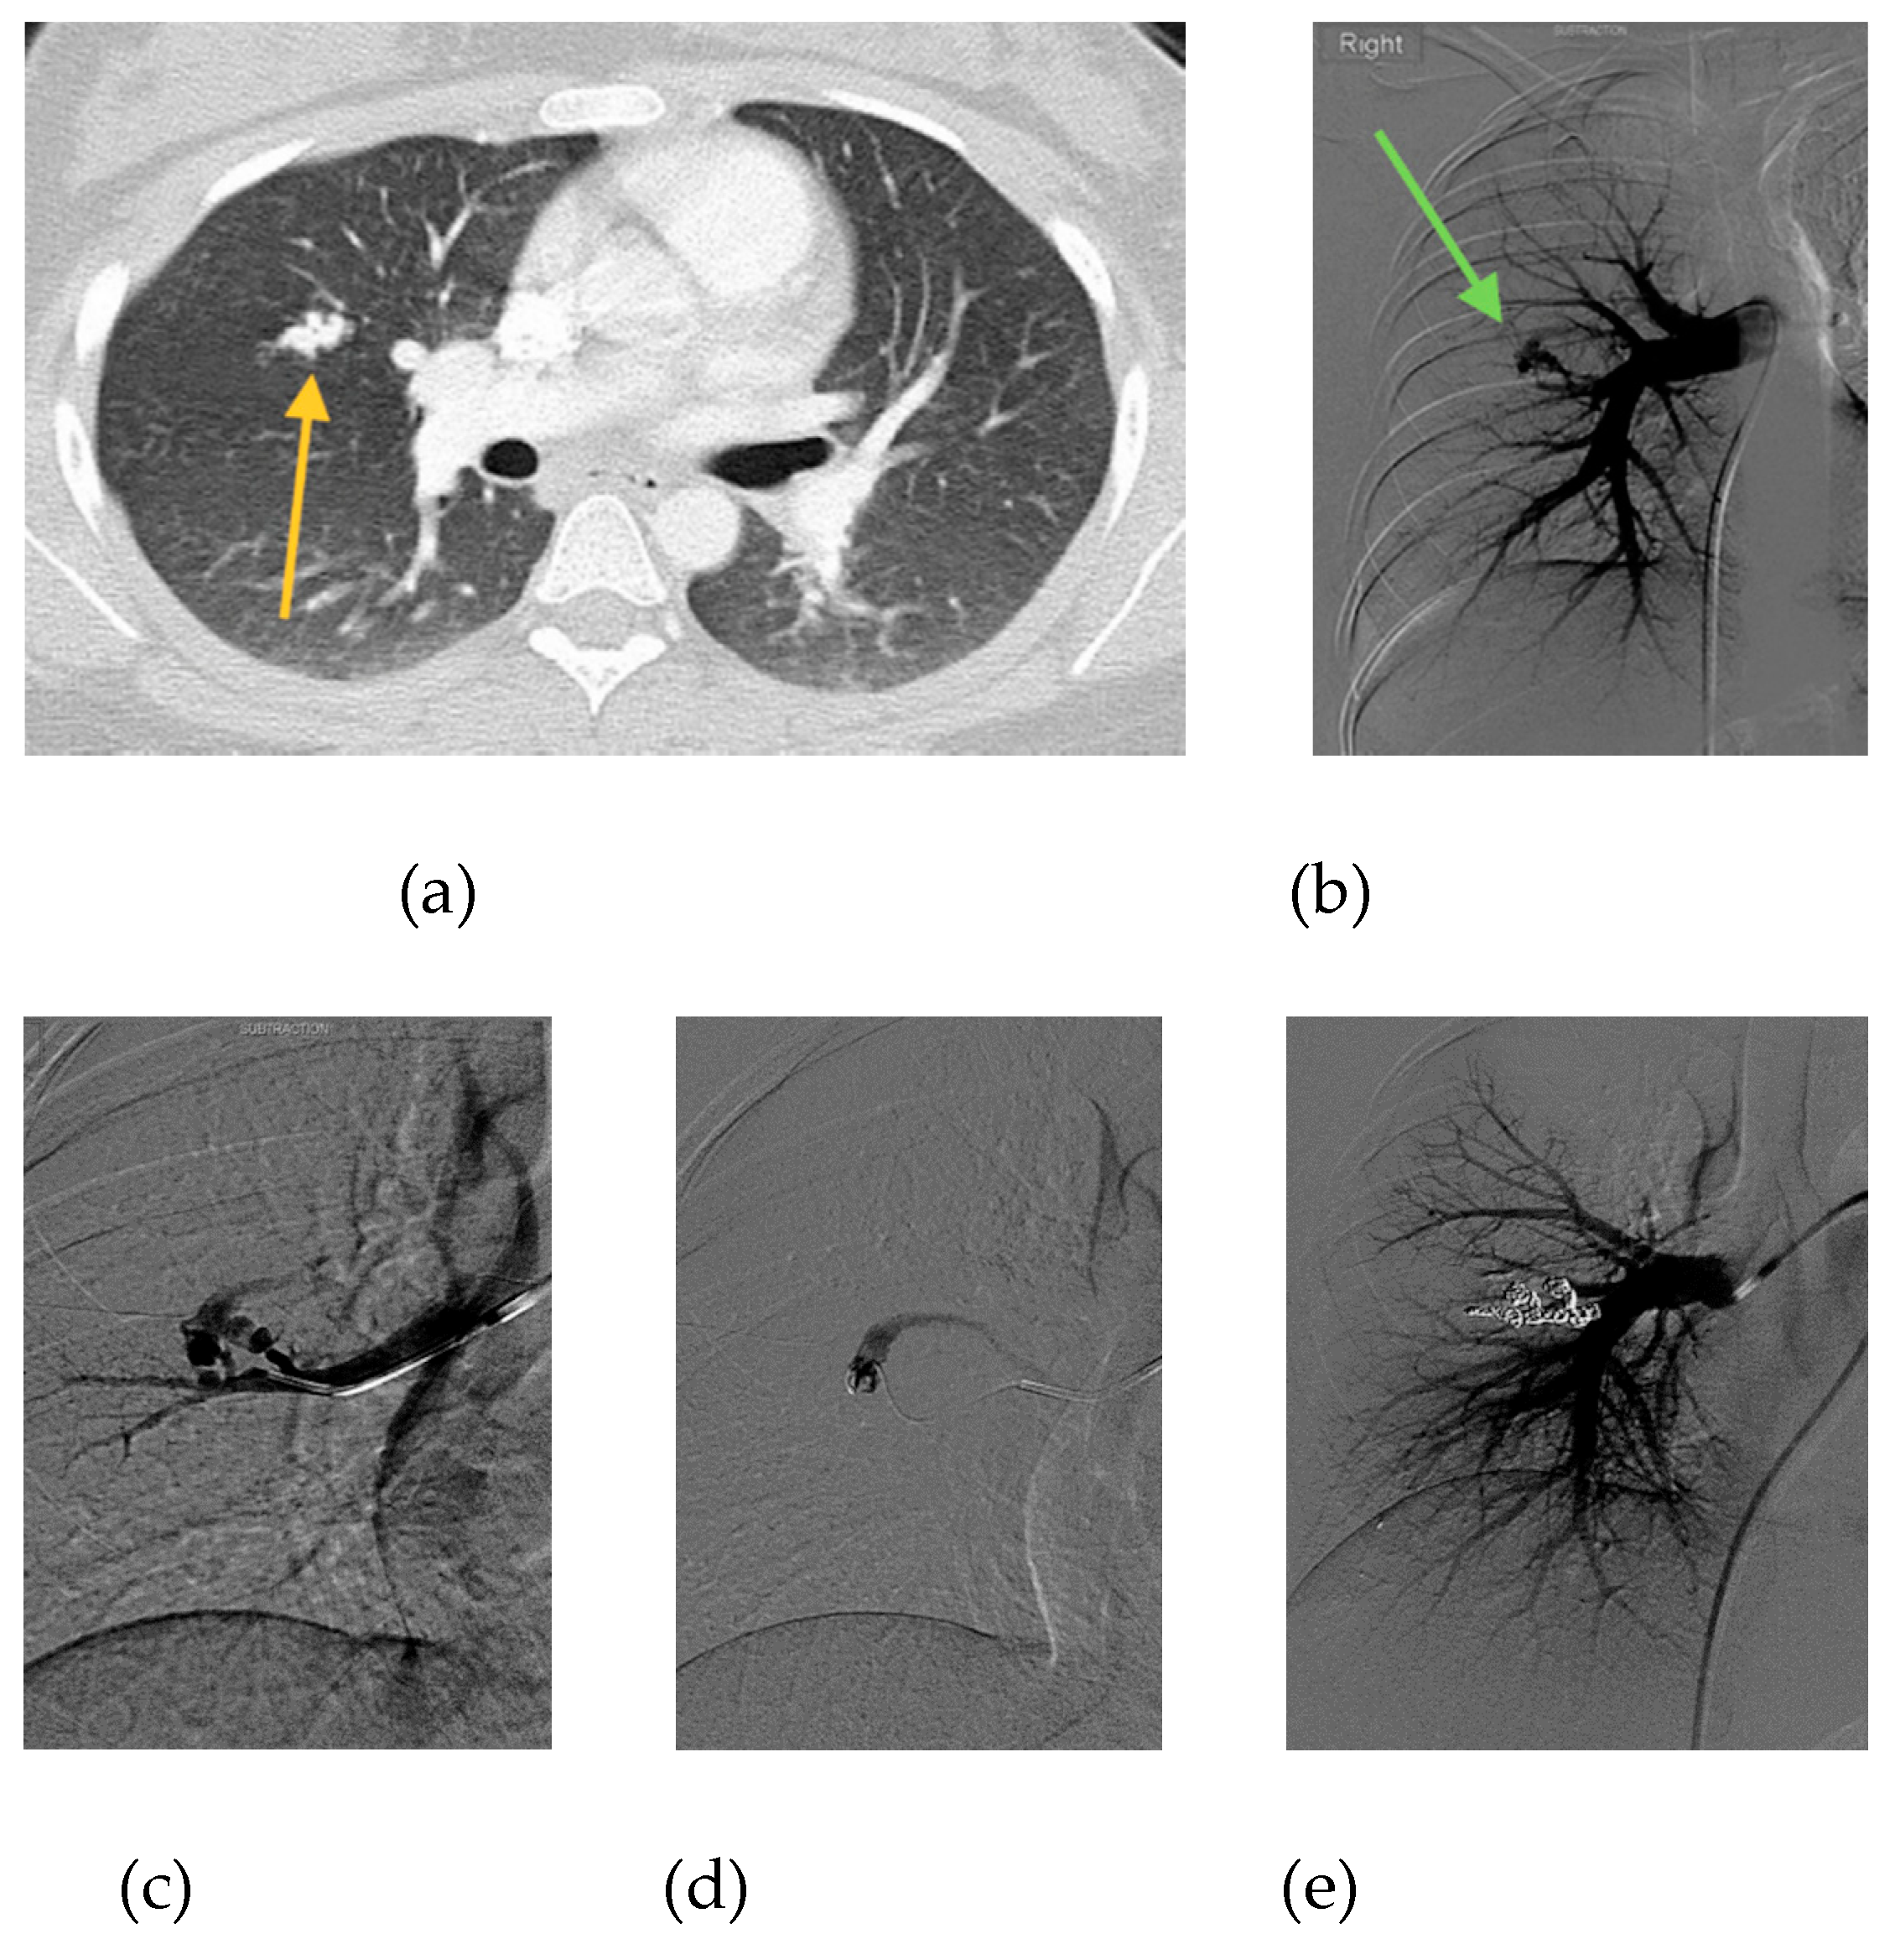

Figure 3.

20-year-old female, who is 6 months pregnant presents with mild dyspnea. (a) Chest CT performed to rule out pulmonary embolism reveals complex PAVM with 3 mm feeding artery (orange arrow). (b) Initial pulmonary angiogram confirms PAVM in the right middle lobe (green arrow). (c) Angiogram shows selection of the supplying artery with a catheter. (d) Microcatheter placement into PAVM nidus. (e) Final angiogram shows complete occlusion of PAVM following embolization with 11 microcoils and 1 microvascular plug. Estimated fetal radiation dose was <5 mGy, scatter only with no direct irradiation. Remainder of pregnancy was uneventful and the patient delivered a healthy baby girl at 39 weeks gestational age.